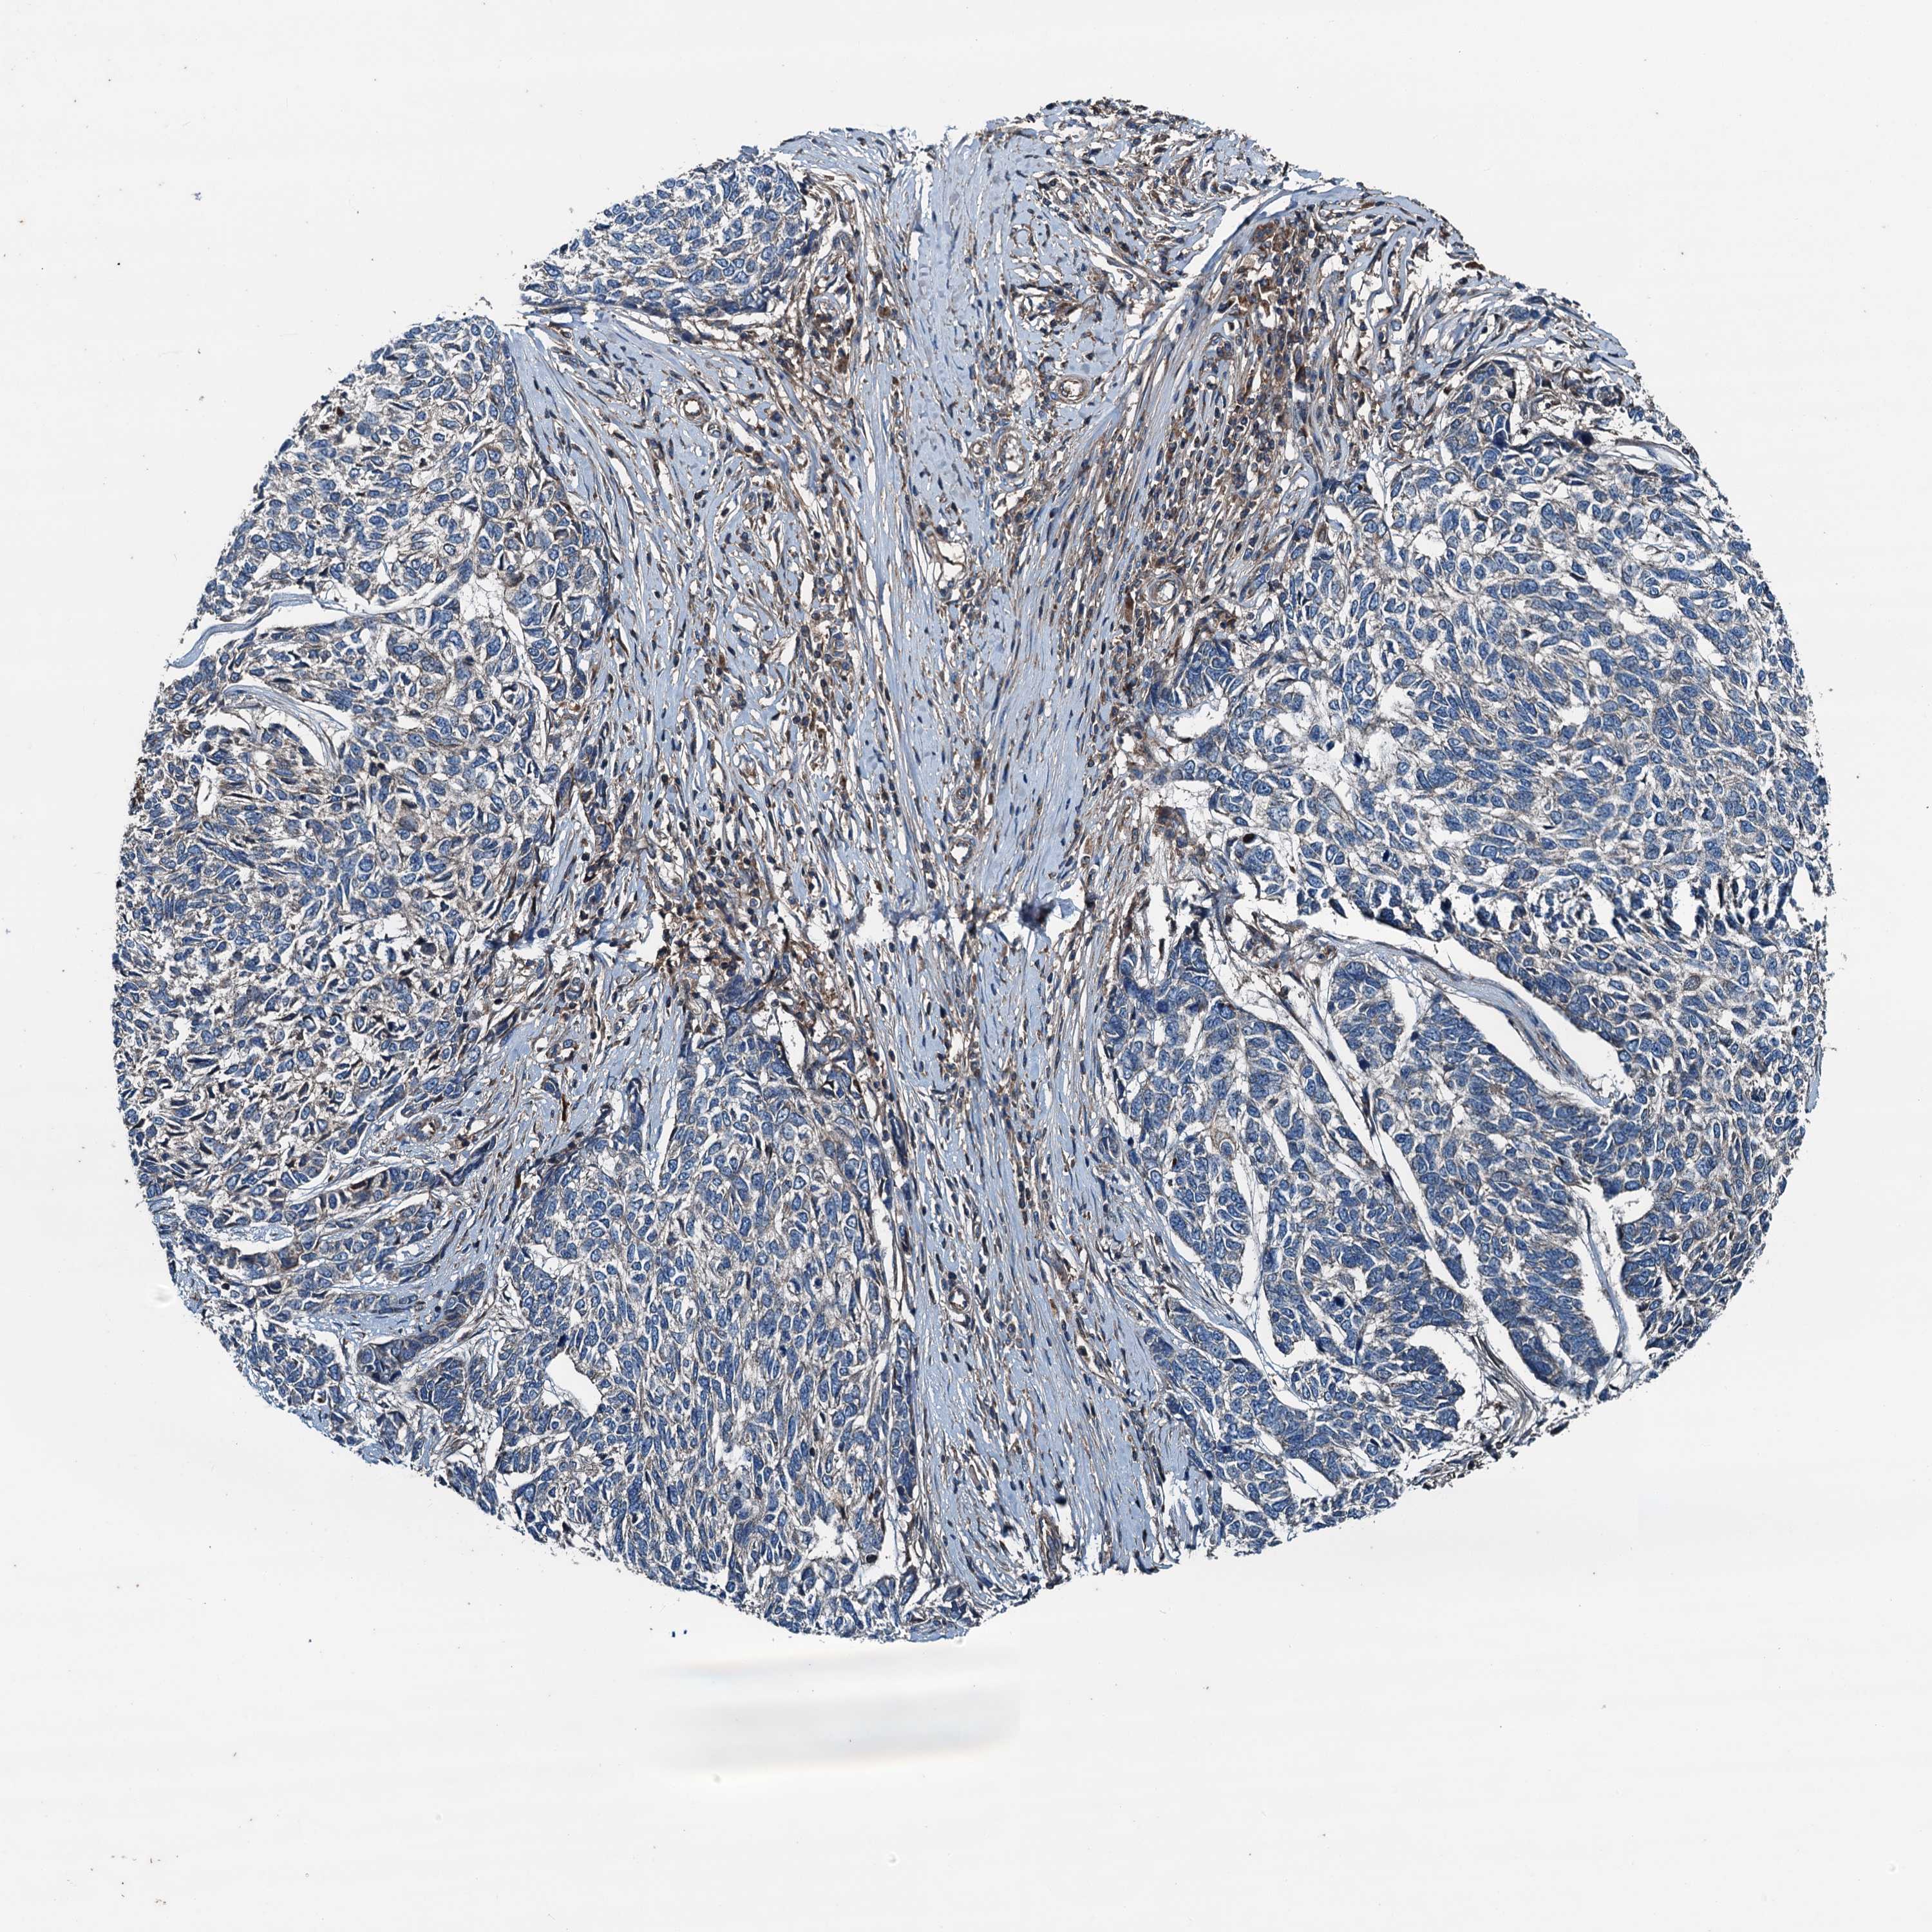

SKIN CANCER - Protein expressioni

A mouse-over function shows sample information and annotation data. Click on an image to view it in a full screen mode. Samples can be filtered based on level of antibody staining by selecting one or several of the following categories: high, medium, low and not detected. The assay and annotation is described here.

Antibody stainingi

Antibody staining in the annotated cell types in the current human tissue is reported as not detected, low, medium, or high, based on conventional immunohistochemistry profiling in selected tissues. This score is based on the combination of the staining intensity and fraction of stained cells.

Each image is clickable and will lead to virtual microscopy that enables deeper exploration of all samples and also displays staining intensity scores, fraction scores and subcellular localization as well as patient and tissue information for each sample.

Antibody HPA041227

Staining

High

Intensity

Strong

Quantity

>75%

Location

Nuclear

Basal cell carcinoma

Squamous cell carcinoma, NOS

Squamous cell carcinoma, metastatic, NOS